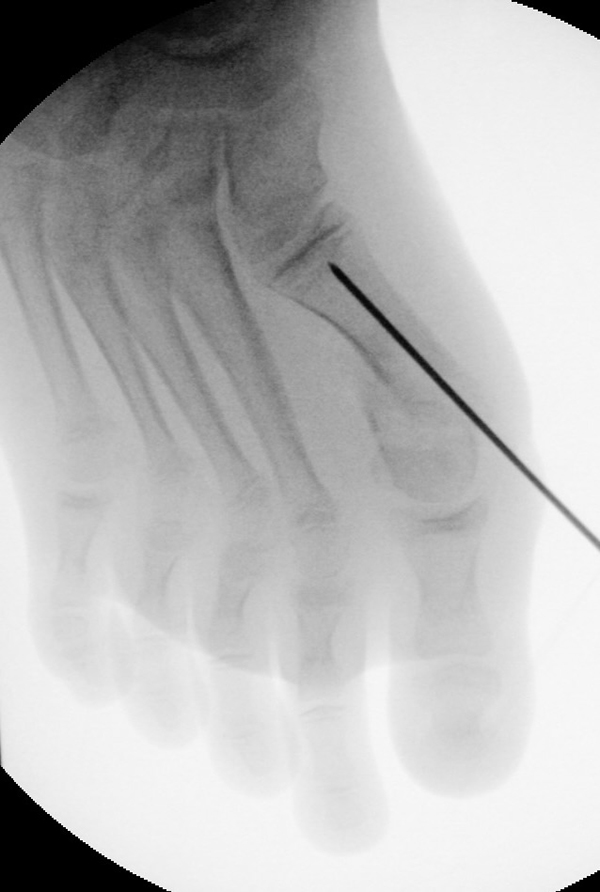

In der minimalinvasiven Fußchirurgie ist es unabdingbar, die Fräse in ihrer Position zum Knochen radiologisch zu kontrollieren, damit vulnerable Wachstumsfugen oder angrenzende Gelenke nicht verletzt werden. Zu diesem Zweck werden mit einem Bildwandler während der Operation die genaue Position der Fräse und der Osteotomieverlauf überprüft, was die Strahlenbelastung im Vergleich zu offenen Verfahren erhöht. Diese Strahlenbelastung hat potenziell einen schädigenden Einfluss auf den noch blutbildenden Knochen von Heranwachsenden. Gesicherte Landmarken am Fuß können die notwendige Zahl der Röntgenbilder und damit die Strahlung minimieren. Ist es erforderlich, mehrere Knochen zu osteotomieren, wie zum Beispiel im Bereich der Kleinzehen, werden anhand der Landmarken kleine Injektionsnadeln auf Höhe der geplanten Osteotomien vorgelegt und radiologisch im Bildwandler (BV) dokumentiert (Abb. 11). Ein solches Bild schafft eine gute Orientierung, sodass auf radiologische Kontrollen intraoperativ weitestgehend verzichtet werden kann.

Abb. 11: Lokalisation mehrerer Stichinzisionen mit einem Röntgenbild.

Zum Lesen der Bildbeschreibung und zur Vollansicht bitte das Bild anklicken. Bild: A. Helmers.